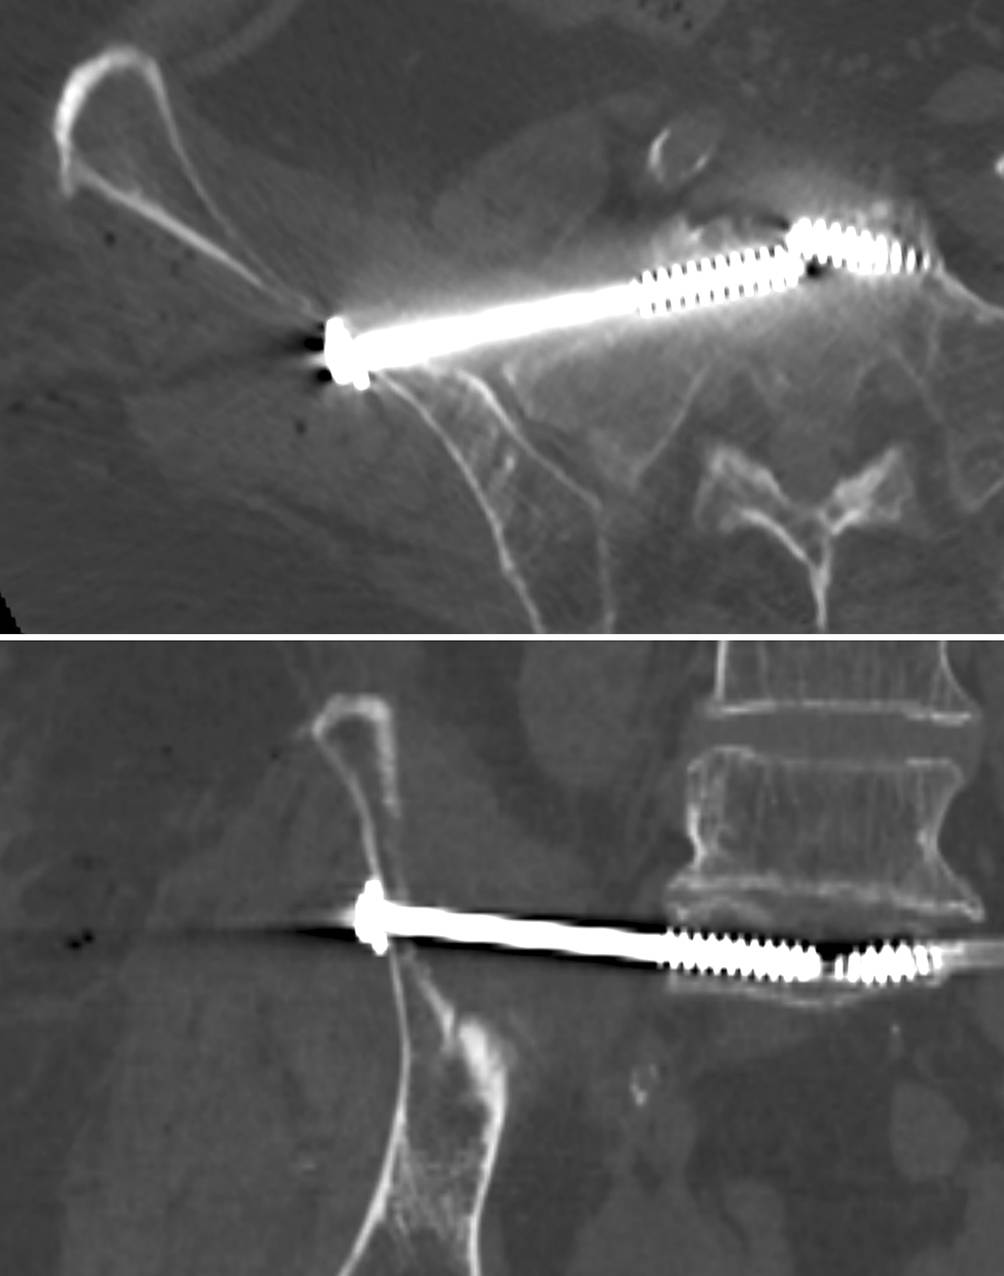

Fig. 7

Advancing the guide wire, predrilling and screw implantation. a The guide wire is advanced across the sagittal midline in transforaminal sacral fractures. In SI joint disruptions the guidewire should be advanced at least to the extent that the thread (16 or 32 mm) is completely medial of the SI joint in order to obtain a lag screw effect. b Predrilling is performed across the SI joint for a total of three cortices. c A cannulated 6.5 mm fully threaded cancellous screw is inserted over the guide wire as a position screw without compression of the transforaminal sacral fracture